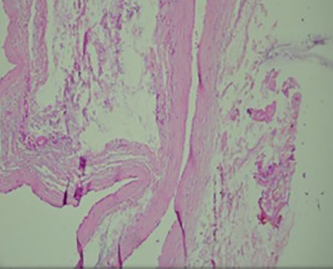

Histopathological examination of parathyroid adenocarcinoma (Courtesy Dr. V. Penopoulos)